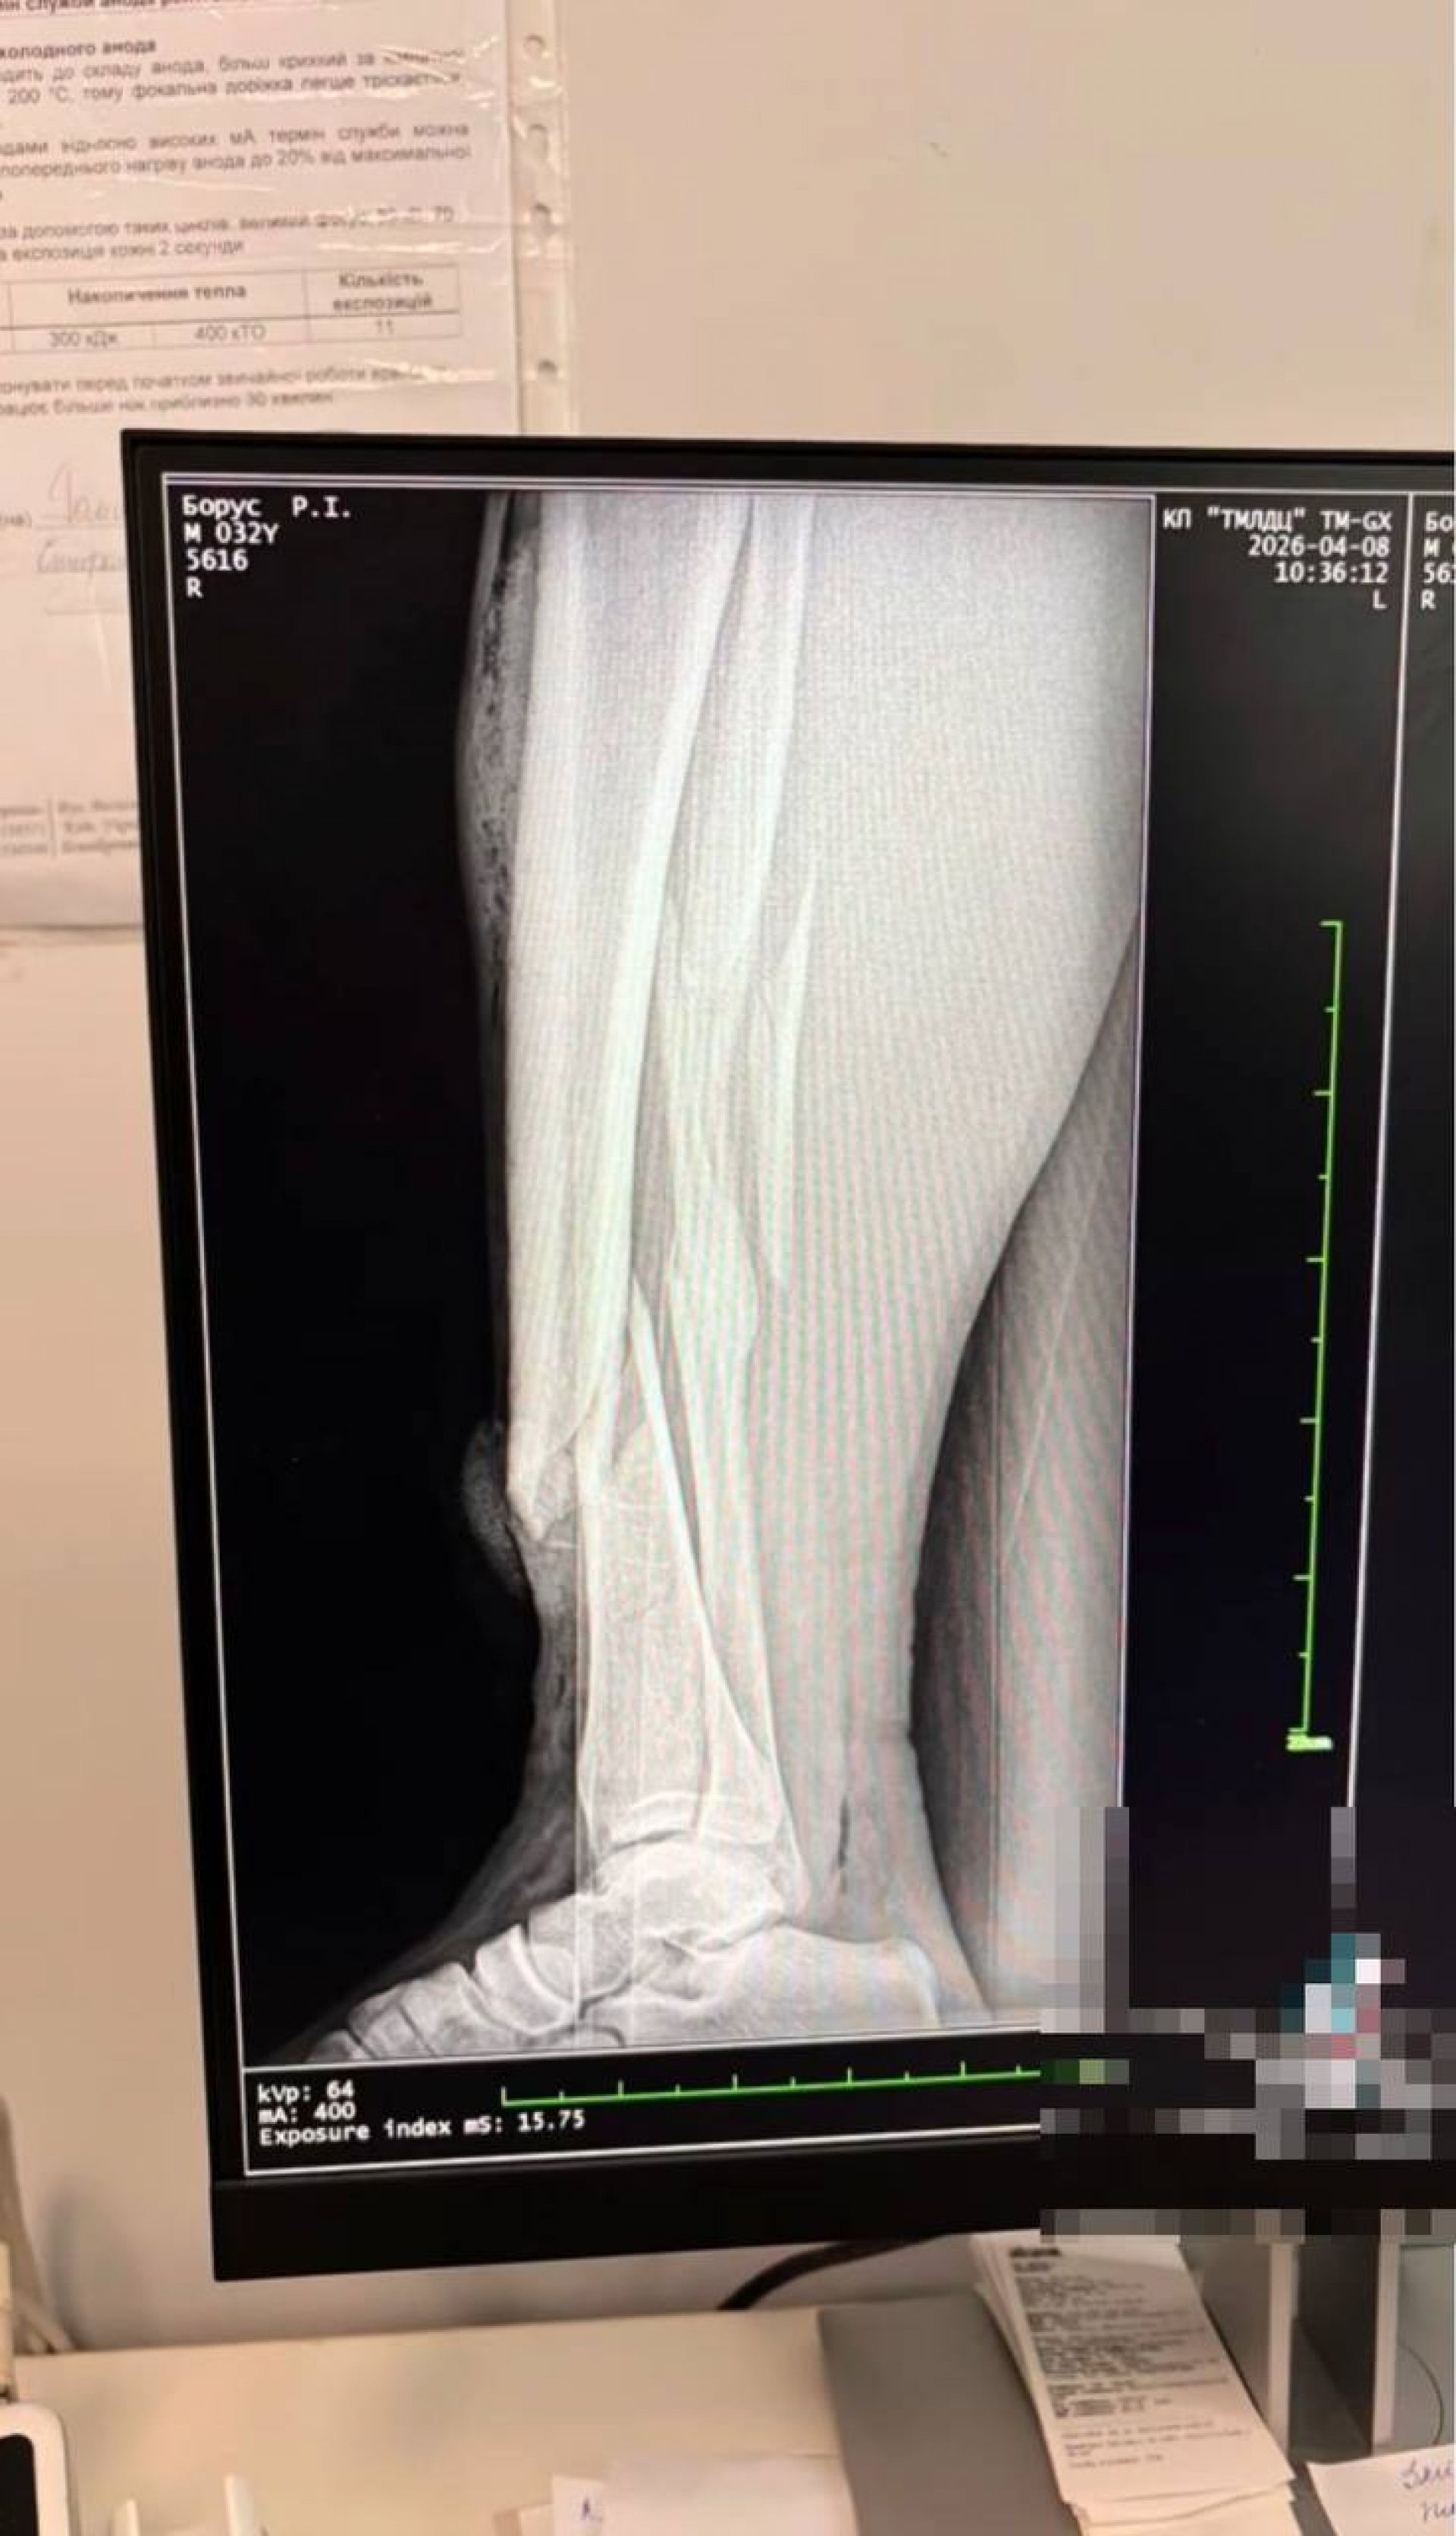

За словами двоюрідного брата, постраждалому вже провели операцію на ногу. Також у соціальних мережах дружина опублікувала рентгенографічні знімки ноги чоловіка після побиття.

За зверненням редакції «20 хвилин» у Спеціалізованій прокуратурі у сфері оборони Західного регіону прокоментували, що інформація про інцидент на вулиці Сахарова, де троє працівників ТЦК та СП завдали тілесних ушкоджень 32-річному місцевому жителю, надійшла 8 квітня орієнтовно о 10:20. У потерпілого діагностували відкритий перелом лівої великогомілкової кістки.